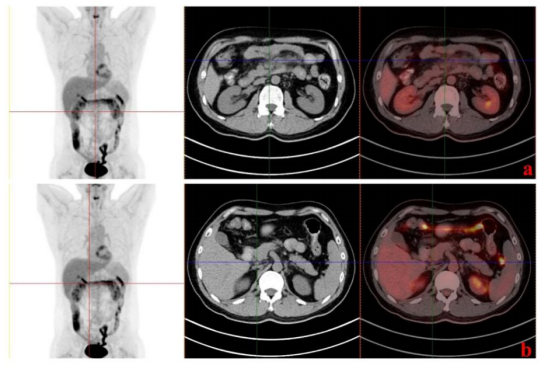

A 40-year-old male patient had no obvious inducement in early May 2021, a palpable mass in the lower abdomen of the xiphoid process, no pain, no nausea, vomiting, weight loss and other discomfort. The patient was diagnosed with lymphoma after CT, tumor puncture, immunohistochemistry and other examinations (Figure 2). The tumors of the lymphostomy system were mainly follicular structures, and follicular B-cell lymphoma was considered as grade 2 and stage 3, with FLIPI score of 2. After several rounds of chemotherapy, the patient's condition improved slightly. On September 5, 2023, the patient's re-examination of PET-CT(Figure 2B-b) indicated that the tumor was in a state of inhibition and partial remission (PR) after treatment, but some lesions still remained, and the attending physician decided to perform CAR-T therapy on the patient.

Figure 2. PET-CT images and pathological sections before CAR-T infusion. (A) Pathological findings of abdominal mass before CAR-T infusion. a: Hematoxylin eosin staining. b-e: Positive for Bcl-2, positive for Bcl-6, positive for CD21, positive for CD20. (B) PET-CT imaging time for initial diagnosis and effective treatment of the abdomen. a:2021-5-26. b: 2021-12-14. (C) PET-CT time and immunomaintenance therapy for recurrent abdomen. a:2023-2-16. b: 2023-9-5.

In addition, we measured the proportion of CD4+/CD8+T cells and found that it increased after a decline on day 60, while the number of CAR copies increased first and then decreased. We speculate that the tumor may have recurred around day 60, dormant CAR T cells are activated, resulting in elevated CAR copy numbers, cytotoxic CD8+ T cells proliferate and kill the tumor, and PET-CT at month four (Figure 5) suggests that the patient has achieved complete response (CR).

Figure 5. PET-CT examination 4 months after infusion